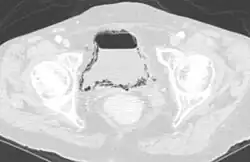

Emphysematous cystitis in computertomography | |

Diagnosis is made by patient history of passing air or a sputtering urine stream. CT scans may show air in the urinary bladder or bladder walls.